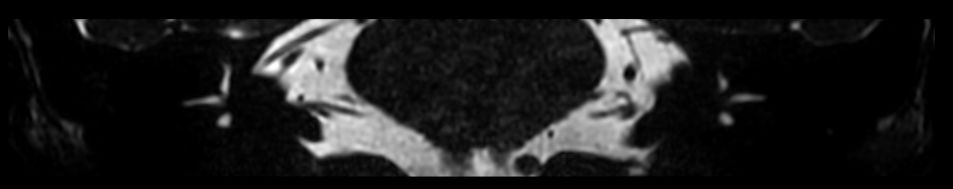

IAC - T2w TSE 3D DRIVE Compressed SENSE

IAC - T2w TSE 3D DRIVE (Right oblique reformat) Compressed SENSE

IAC - T2w TSE 3D DRIVE (Right Spin MIP) Compressed SENSE

IAC - T2w TSE 3D DRIVE (Left oblique reformat) Compressed SENSE

IAC - T2w TSE 3D DRIVE (Left Spin MIP) Compressed SENSE